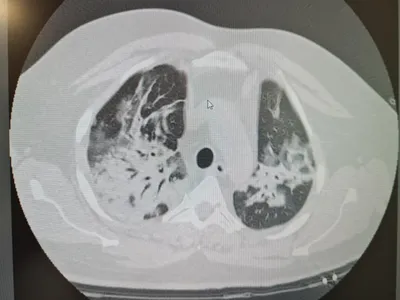

FOTO Cum arată plămânii unui tânăr cu COVID, în stare gravă la spital, după tratament cu ivermectină

Dr. Elena Copaciu, medic primar ATI, a publicat, pe pagina sa de Facebook, imagini cu plămânii unui tânăr care s-a tratat cu ivermectină (medicament de uz veterinar).